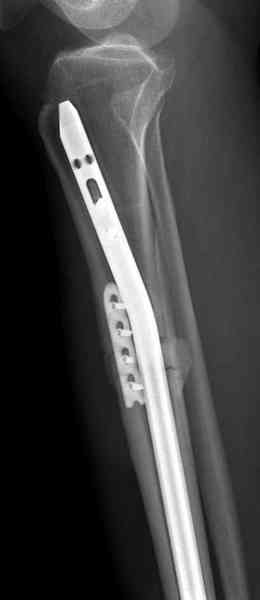

conference мы разбирали похожий случай, ложный сустав большеберцовой кости после резекции опухоли.

К нашему онкологу-ортопеду обратился больной с жалобами на боли в голени, из рассказа - год назад была сделана биопсия большеберцовой кости, но название заболевания "не запомнил”.

Оперирован в военном госпитале с заменой сегмента

аллокостью большеберцовой кости и после демобилизации явился для постоянного наблюдения по месту жительства.

Наши имели проблему со сращением, пришлось им сделать динамизацию, дополнительную аутопластику.

Снимки представлены.